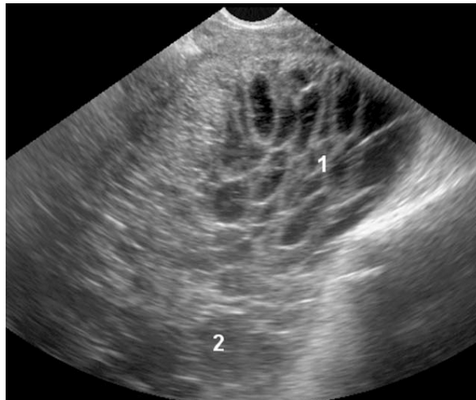

Опухоль Крукенберга (только метастатический рак желудка)

Рак Крукенберга характеризовался, как овариальная опухоль неоднородной эхоструктуры с преимущественно изоэхогенными и гипоэхогенными участками, а также с потенциальным появлением некроза (рис.5) с неровным внутренним контуром, но с гладкой поверхностью. Васкуляризацию опухолей Крукенберга (вне зоны потенциального некроза) оценивали как гиперваскуляризованную.

Рис.5. Опухоль Крукенберга (метастазы рака желудка): твердая (солидная), с неровной внутренней поверхностью и гладкой поверхностью; гетерогенная опухоль, которая является в основном изоэхогенной, однако визуализируются гиперэхогенные (1) и гипоэхогенные (2) участки.